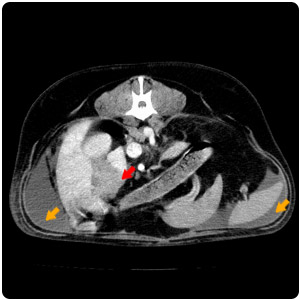

| 腹腔腫塊(紅)、腹水(黃) |

腹水(紫)、腹部腫塊(紅)、子宮殘段(黃) |